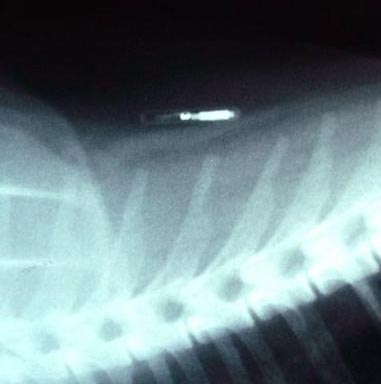

Seamus underwent emergency surgery, and doctors extracted a 4-pound, 3-ounce tumor from the dog. They used four drains to remove fluid from the area in which the tumor had developed. The veterinarian informed the dog's owner, Howard Gillis, that there had been two microchips embedded in Seamus – one presumably inserted by the dog's breeder when Seamus was only 9 months old. The chips were both located in and around the tumor.

Albrecht told the story of another dog, a 5-year-old Yorkshire terrier named Scotty that was diagnosed with cancer in Memphis, Tenn. Scotty developed a tumor between his shoulder blades, in the same location where the microchip had been implanted. The tumor the size of a small balloon – described as malignant lymphoma – was removed. Scotty's microchip was embedded inside the tumor.